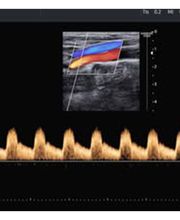

Il Dott. Andrea Velati è Medico Chirurgo e specialista in Angiologia Medica dal 1998. Con una solida esperienza, si occupa della diagnosi e del trattamento delle patologie vascolari, arteriose, venose e linfatiche, garantendo un approccio professionale e personalizzato per ogni paziente. Tra i servizi offerti rientrano l'Ecocolordoppler di tutti i distretti vascolari, comprese carotidi, arti inferiori e superiori, e aorta addominale. Diagnosi e trattamento delle patologie delle carotidi. Gestione di patologie arteriose e venose, come l'arteriopatia obliterante e la malattia venosa. Diagnosi e cura di linfedemi degli arti inferiori. Individuazione e monitoraggio di aneurismi dell'aorta addominale. Il Dott. Velati si impegna a offrire soluzioni efficaci e mirate per preservare la salute vascolare dei suoi pazienti, utilizzando tecnologie avanzate e un approccio centrato sulle esigenze individuali.